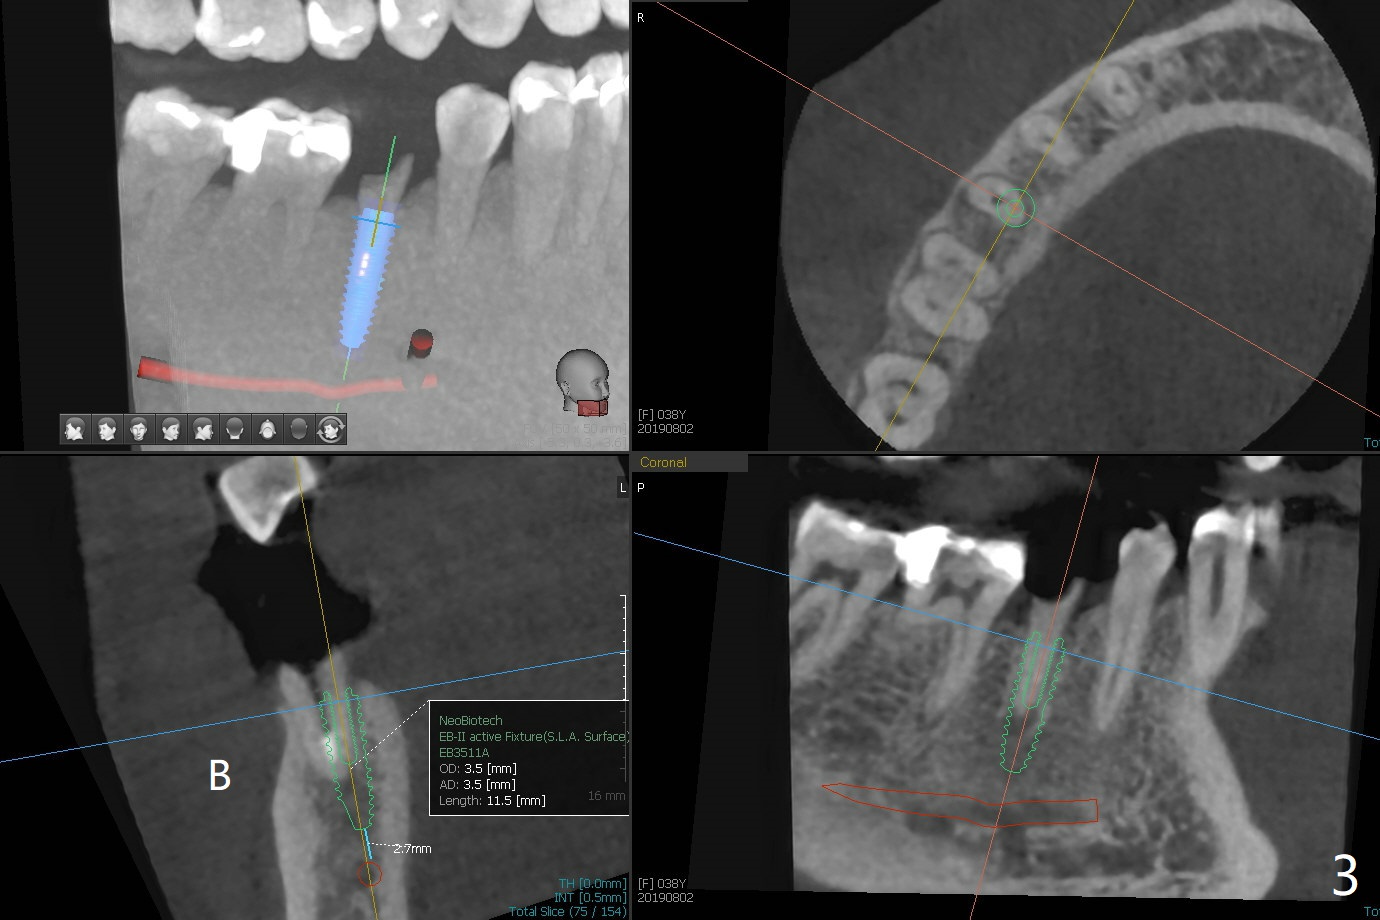

Equigingival Fracture M

A 38-year-old woman dislodged the crown and post of #29 with equigingival root (Fig.1) and incomplete RCT probably related to the curved and obliterated root tip (Fig.2). For restoration, it is the best to initiate osteotomy in the lingual slope of the socket (Fig.3). A 4 mm implant may be more appropriate than 3.5 mm one. Are we ready for free hand placement? Prepare gingival retraction cord for #28 distal cervical caries before surgery (Fig.2 <).